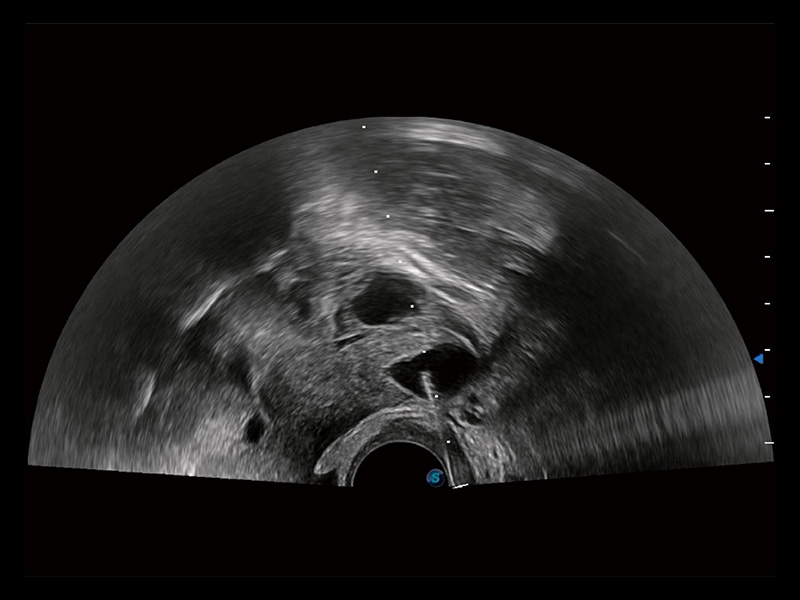

临床图

子宫内膜息肉

输卵管间质部妊娠